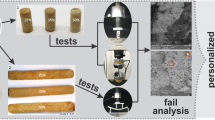

Compressive Test

To investigate the mechanical behavior under load, the implants were tested according to the standard DIN 50134 using a Z010 testing machine (Zwick GmbH & Co. KG, Ulm, Germany). The load velocity was adjusted to 10−2 s−1. The ratio of length to diameter deviates from the standard of 1.5–2. The ratio used was chosen according to necessary size for the rabbits (length: 5 mm, diameter: 4 mm).

Compressive Tests

As shown in the force-strain-curves in Fig. 7 and the corresponding values in Table 1, with 341 N and 383 N, respectively, the compression yield point FdF in both structures is well above the expected load of 60 N in the rabbit tibia, in which the implants should be inserted. After the elastic limit there is a long region of plastic deformation until the structure collapses. Depending on the structure, the implants have compressive strength of 1608 or 1921 N, with a corresponding deformation of 21.4 or 33.2%.

Based on the compression tests, the assumption made after the simulation, that the structures made of LAE442 are stable enough can be confirmed. The magnesium sponges in Figs. 4 and 5 have enough strength for the application as an implant in a rabbit tibia. Here the yield point is in both cases much larger than the required 60 N.